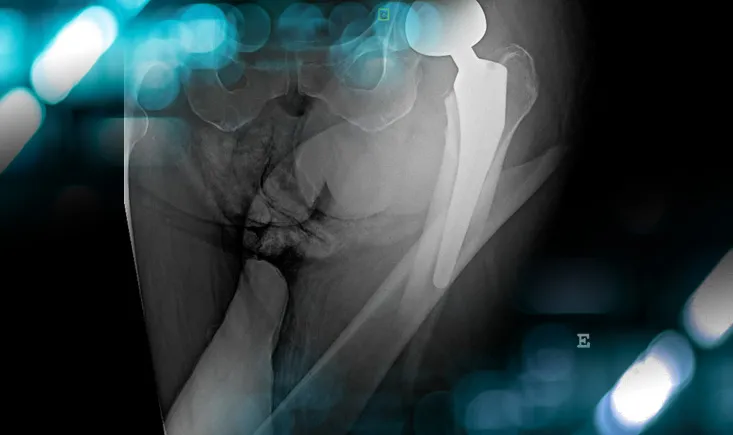

Management of an osteolytic lesion of the distal femur affecting the knee joint

Explore the case of a patient with knee pain, revealing more than just an injury, and uncover the management strategies for osteolytic lesions…